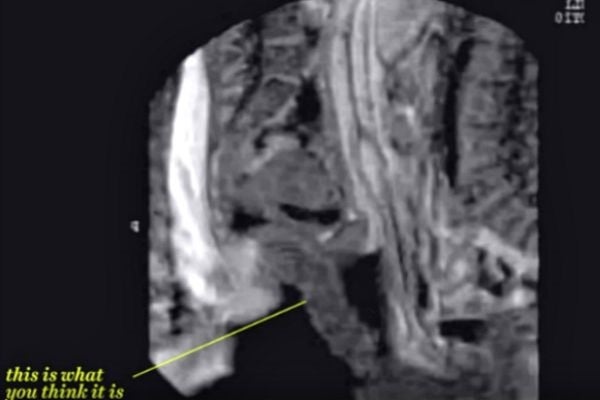

3. No, your eyes aren't deceiving you.

Yep, put that on your list of "things I never thought I'd see, and probably never want to see again."